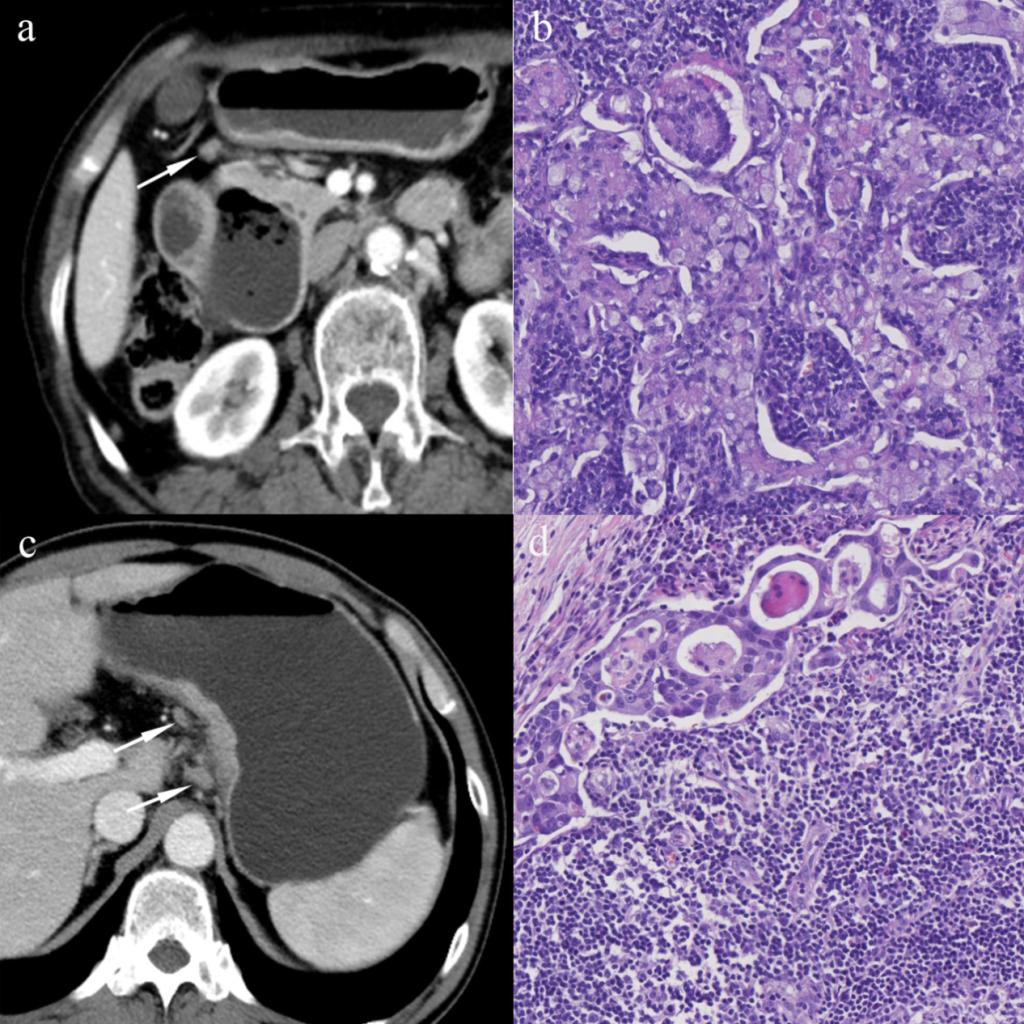

圖1 區(qū)域淋巴結的CT及病理影像